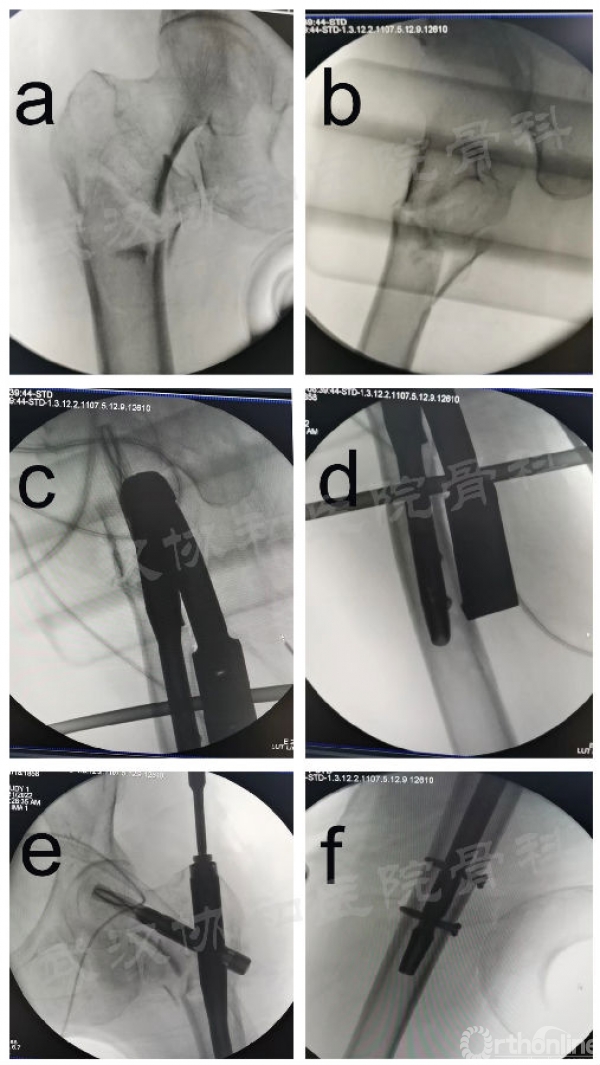

术中DRTR应用图

术中透视图。DRTR复位后股骨转子间骨折前后位(a)和外侧位(b)影像学图;(c、d) 置钉后的侧位图;(e、f) 置钉后的前后位图